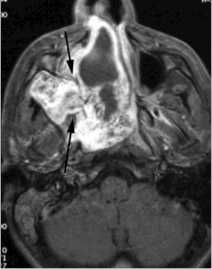

КТ височных костей выявила наличие двухсторонней аномалии развития улитки в виде неполного разделения I типа (табл. 4). При этом данное утверждение верно как для левого, так и для правого уха, несмотря на различную, на первый взгляд, картину (рис.1).

Рис. 1. Данные КТ пациентки К.

Примечание: Так, справа (1) улитка представлена небольшой полостью, максимальный размер которой составляет не более 5 мм, преддверие и полукружные каналы отсутствуют. Слева (2) улитка представлена единой полостью без внутренней архитектуры, отмечается наличие расширенного преддверия (рис. 2, стрелка); расширенная система полукружных каналов (рис. 3, стрелка).